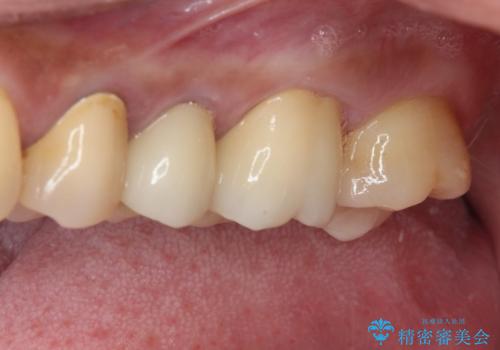

億劫に感じて治療を先延ばししていたそうですが、始めてみるとスムーズに治療が終わり、早く始めておけば良かったと仰っていました。

他にも加療の必要な歯があるので、定期健診を行いながら再開していく予定です。